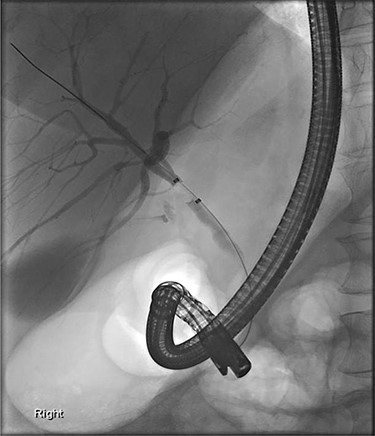

Further examination led to a diagnosis of DCBD with a separate left intra- and extrahepatic bile duct with ectopic drainage into the stomach. Magnetic resonance cholangiopancreatography (MRCP) revealed marked left intrahepatic duct (IHD) dilatation. The left IHDs were draining via an aberrant extra-hepatic bile duct into the pre-pyloric region. The left and right hepatic ducts did not communicate. It also demonstrated pancreatic divisum and multiple side branch intra-ductal papillary mucinous neoplasms (IPMN) (Fig. 3). Endoscopic retrograde cholangiopancreatography (ERCP) confirmed the MRCP findings but also revealed an intraluminal-filling defect in the left IHD (Figs 4 and 5).

ERCP: cannulation via the major papilla orifice into the CBD draining the right IHDs. There was no communication between the ACBD and the right IHDs.

ERCP: cannulation via the pre-pyloric fistula opening. Contrast outlining the ACBD and the left IHDs.